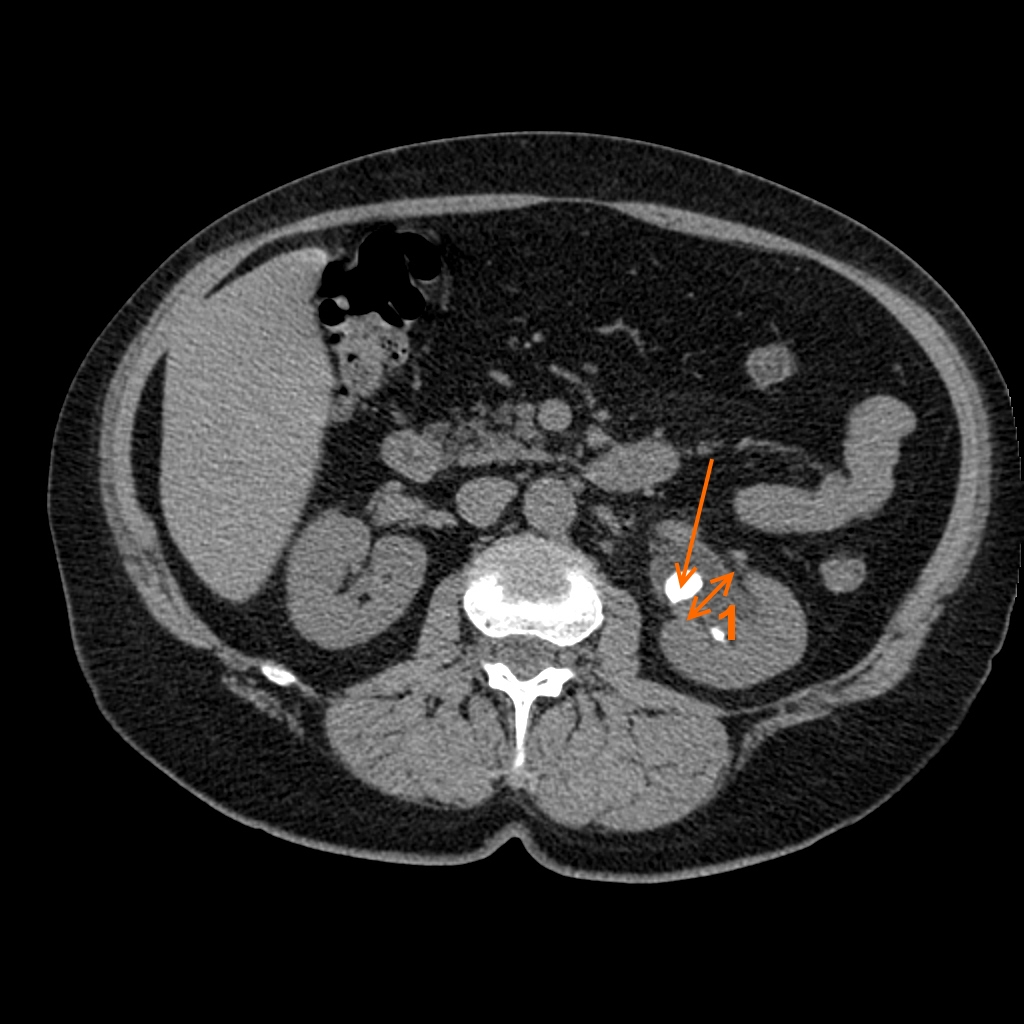

КТ ретроперитонеального фиброза: Изображения и диагностика